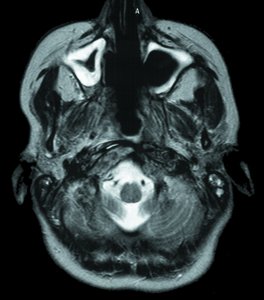

To date, ion-beam radiotherapy has been used to treat more than 440 patients for tumors in the head or neck region. The advantage of this new treatment modality is that the ion beam selectively damages tumor tissues while sparing the surrounding healthy tissues.

Further research will focus on applying the new treatment method to other malignant tumors as well.